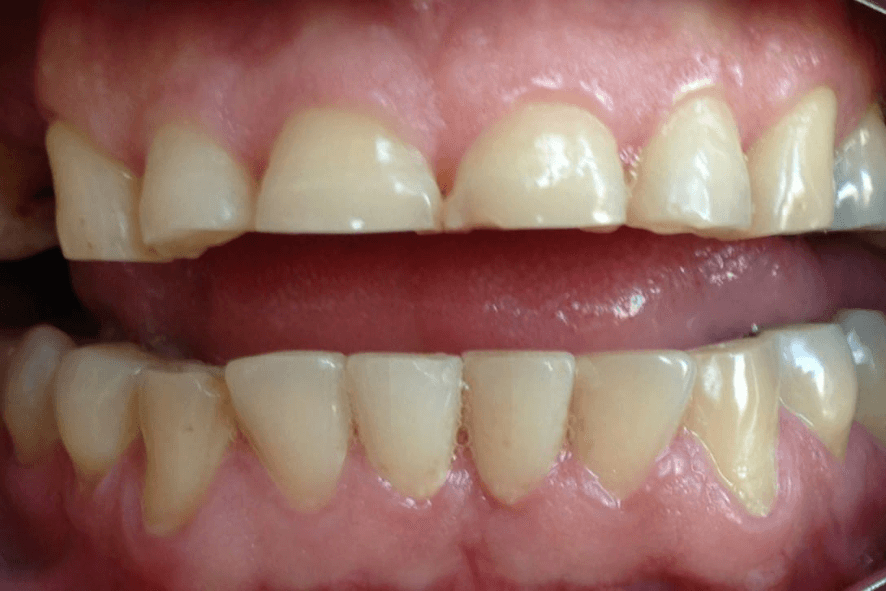

🔹 Desgaste dos dentes

- Sintomas do bruxismo: desgaste dos dentes, dor ao mastigar, dor de cabeça ao acordar, sensibilidade nos dentes, estalos na mandíbula.

7) O que acontece se não cuidar do bruxismo?

Ignorar o bruxismo pode levar a desgaste acentuado dos dentes, fraturas dentárias, retração gengival, dor crônica, DTM e até perda dentária. Além disso, os músculos faciais podem ficar constantemente tensos, piorando a qualidade de vida.

10) O que é placa de bruxismo? Para que serve?

A placa de bruxismo, também chamada de placa miorrelaxante, é um dispositivo feito sob medida para proteger os dentes e aliviar a tensão da mandíbula durante o sono. Ela evita o desgaste dentário e contribui para reduzir dores musculares causadas pelo apertamento e o ranger dos dentes.

11) Placa de bruxismo resolve DTM ou só protege os dentes?

A placa tem duas funções: proteger os dentes contra desgaste e ajudar a relaxar os músculos da mandíbula. Em muitos casos, ela também reduz sintomas da DTM, mas não substitui outros tratamentos quando a disfunção está em estágio avançado.

13) Placa de silicone x acrílico: qual é melhor?

A placa de silicone não é recomendada para o tratamento do bruxismo. Apesar de ser mais macia e parecer confortável no início, ela se desgasta rapidamente, deforma com facilidade e pode até prejudicar a posição dos dentes e aumentar danos na articulação (ATM). A placa de acrílico, ao contrário, é rígida, resistente e oferece o ajuste correto para proteger os dentes e relaxar a musculatura. Na Clínica Odontológica Santé, utilizamos apenas placas de acrílico personalizadas feitas com impressão 3D e odontologia digital, pois garantem eficácia real, maior durabilidade e segurança no tratamento do bruxismo e da DTM.